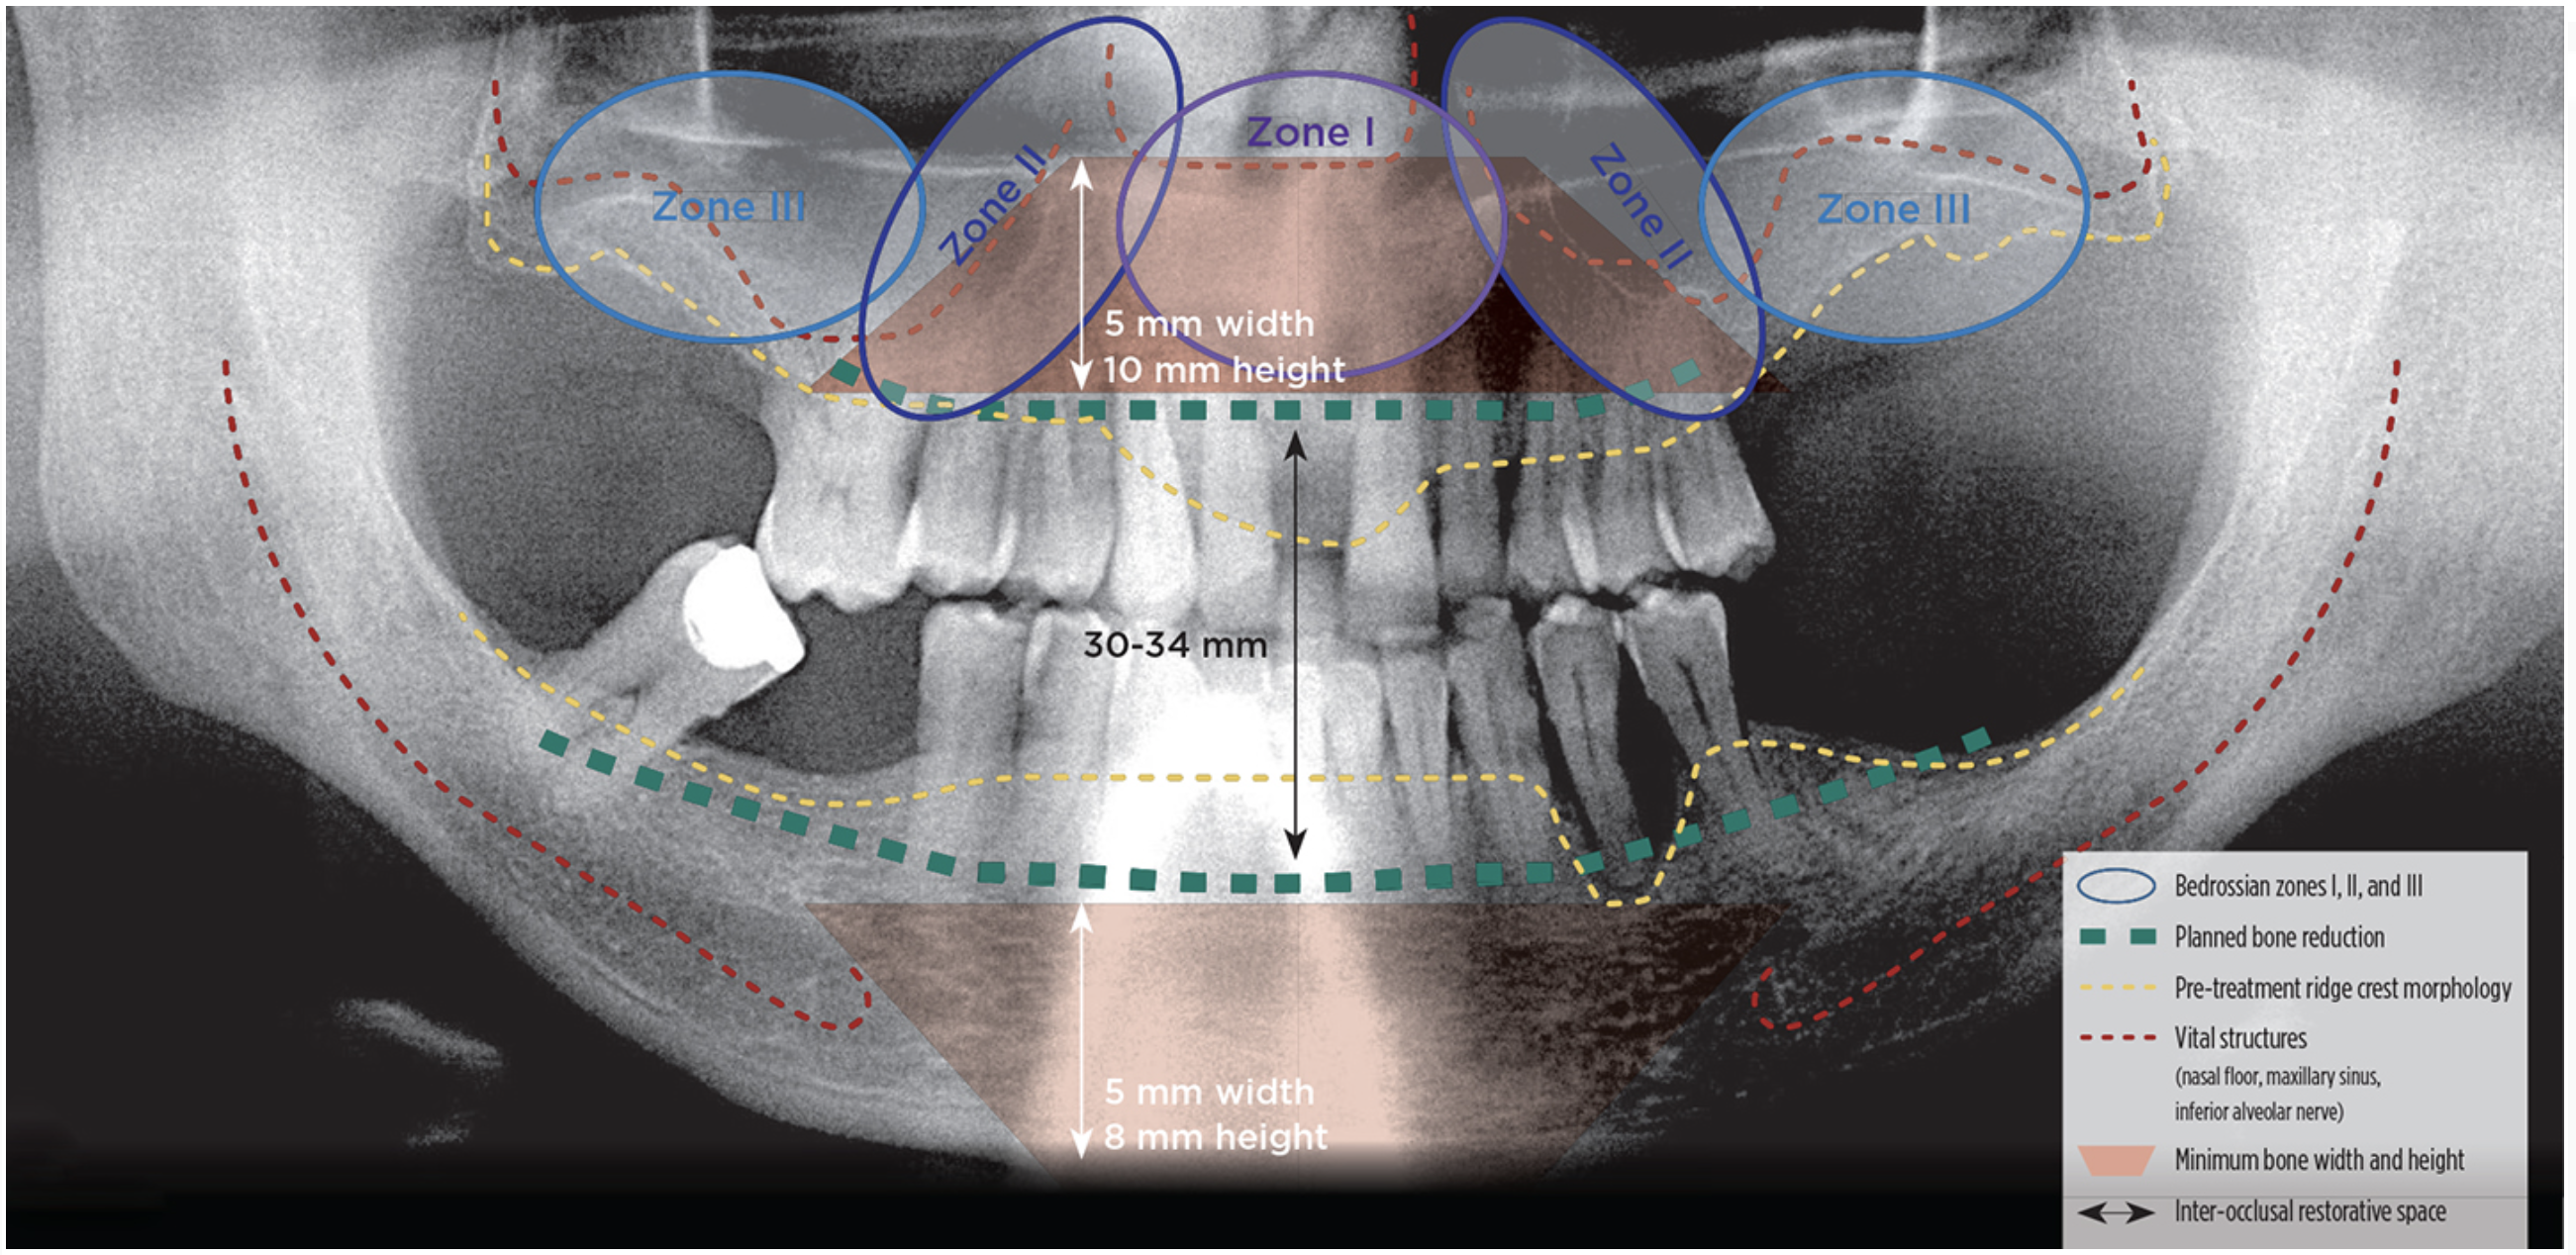

Radiographic Diagnosis and Treatment Planning Survey

• Presence of adequate bone in Bedrossian zones I (pre-maxilla) and II (bicuspid region)

• Location of vital structures, mental nerve, and maxillary sinus

• Presence of composite ridge defects (ridge defect with missing hard and soft tissues)

• Inter-arch space measured between maxillary and mandibular ridge crests at patient’s VDO

• Estimated need for bone reduction to create required inter-occlusal restorative space

• Alveolar ridge width ≥ 5 mm and height ≥ 8 mm in the anterior mandible

• Alveolar ridge width ≥ 5 mm and height ≥ 10 mm in the anterior maxilla

• Bone density classification at primary and backup implant sites

• Verify adequate medullary bone volume for biologic integration at implant sites

• Absence of sinus pathology and patent osteomeatal complex

Diagnostically Driven Treatment Planning

Once the surgeon and the restorative dentist have consulted with the patient and performed a pre-treatment patient evaluation, interdisciplinary treatment planning to identify treatment options for the patient’s dental rehabilitation is completed. The surgeon should have completed and documented a dentofacial and intraoral patient evaluation as well as a radiographic diagnosis and treatment planning survey using cone beam computed tomography (CBCT) (Figure 1) to explore possible treatment options from a surgical perspective. After review of this information, the restorative dentist performs model-based diagnosis and treatment planning. The clinicians jointly review the surgical and restorative treatment planning information and select the treatment option that can be strongly recommended, as well as viable alternatives, for patient education and case presentation.

Fig 1. Radiographic diagnosis and treatment planning survey.

Figure 1